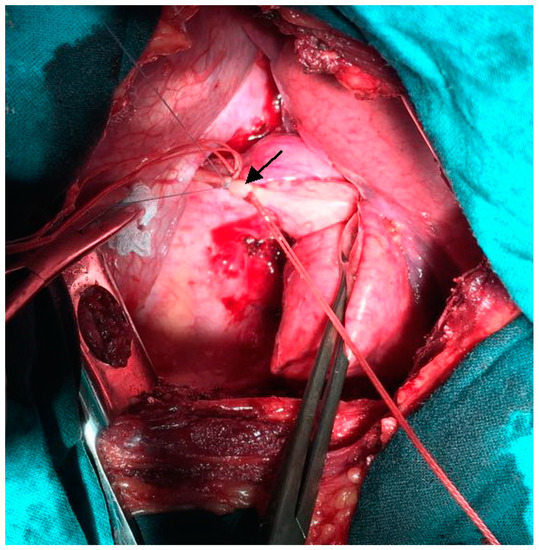

We performed left-sided posterolateral thoracotomy in the seventh intercostal space. The intrapulmonary sequester was characterized by an unventilated area of lung tissue at the posterior-basal segment (S10) of the inferior lobe. In accordance with CT findings, the pulmonary sequester was supplied by an arterial vessel with a diameter of 5 mm. The artery traversed the diaphragm. We ligated the artery carefully before transection (Figure 3).

Figure 3.

Intra-operative photograph: Ligation of the anomalous feeding artery (indicated by arrow) supplying the pulmonary sequester.